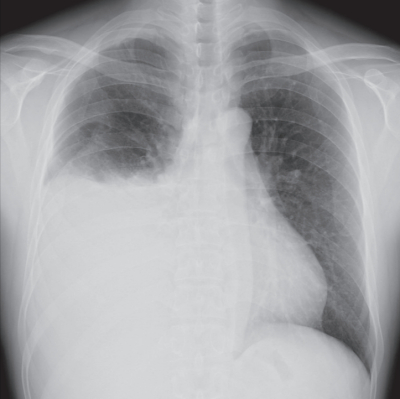

血液所見:赤血球 549万、Hb 16.1 g/dL、Ht 48 %、白血球5,800、血小板 36 万。血液生化学所見:総蛋白 6.6 g/dL、 アルブミン 3.9 g/dL、 総ビリルビン 0.6 mg/dL、AST 22 U/L、ALT 24 U/L、LD 223 U/L(基準 120~245)、 尿素窒素 20 mg/dL、 クレアチニン0.7 mg/dL、Na 138 mEq/L、K 4.7 mEq/L、Cl 105 mEq/L、CEA 3.8 ng/mL(基準 5 以下)。CRP 0.2 mg/dL。胸水中のヒアルロン酸は 150,000 ng/mL と著明な増加を認めた。胸部エックス線写真を別に示す。